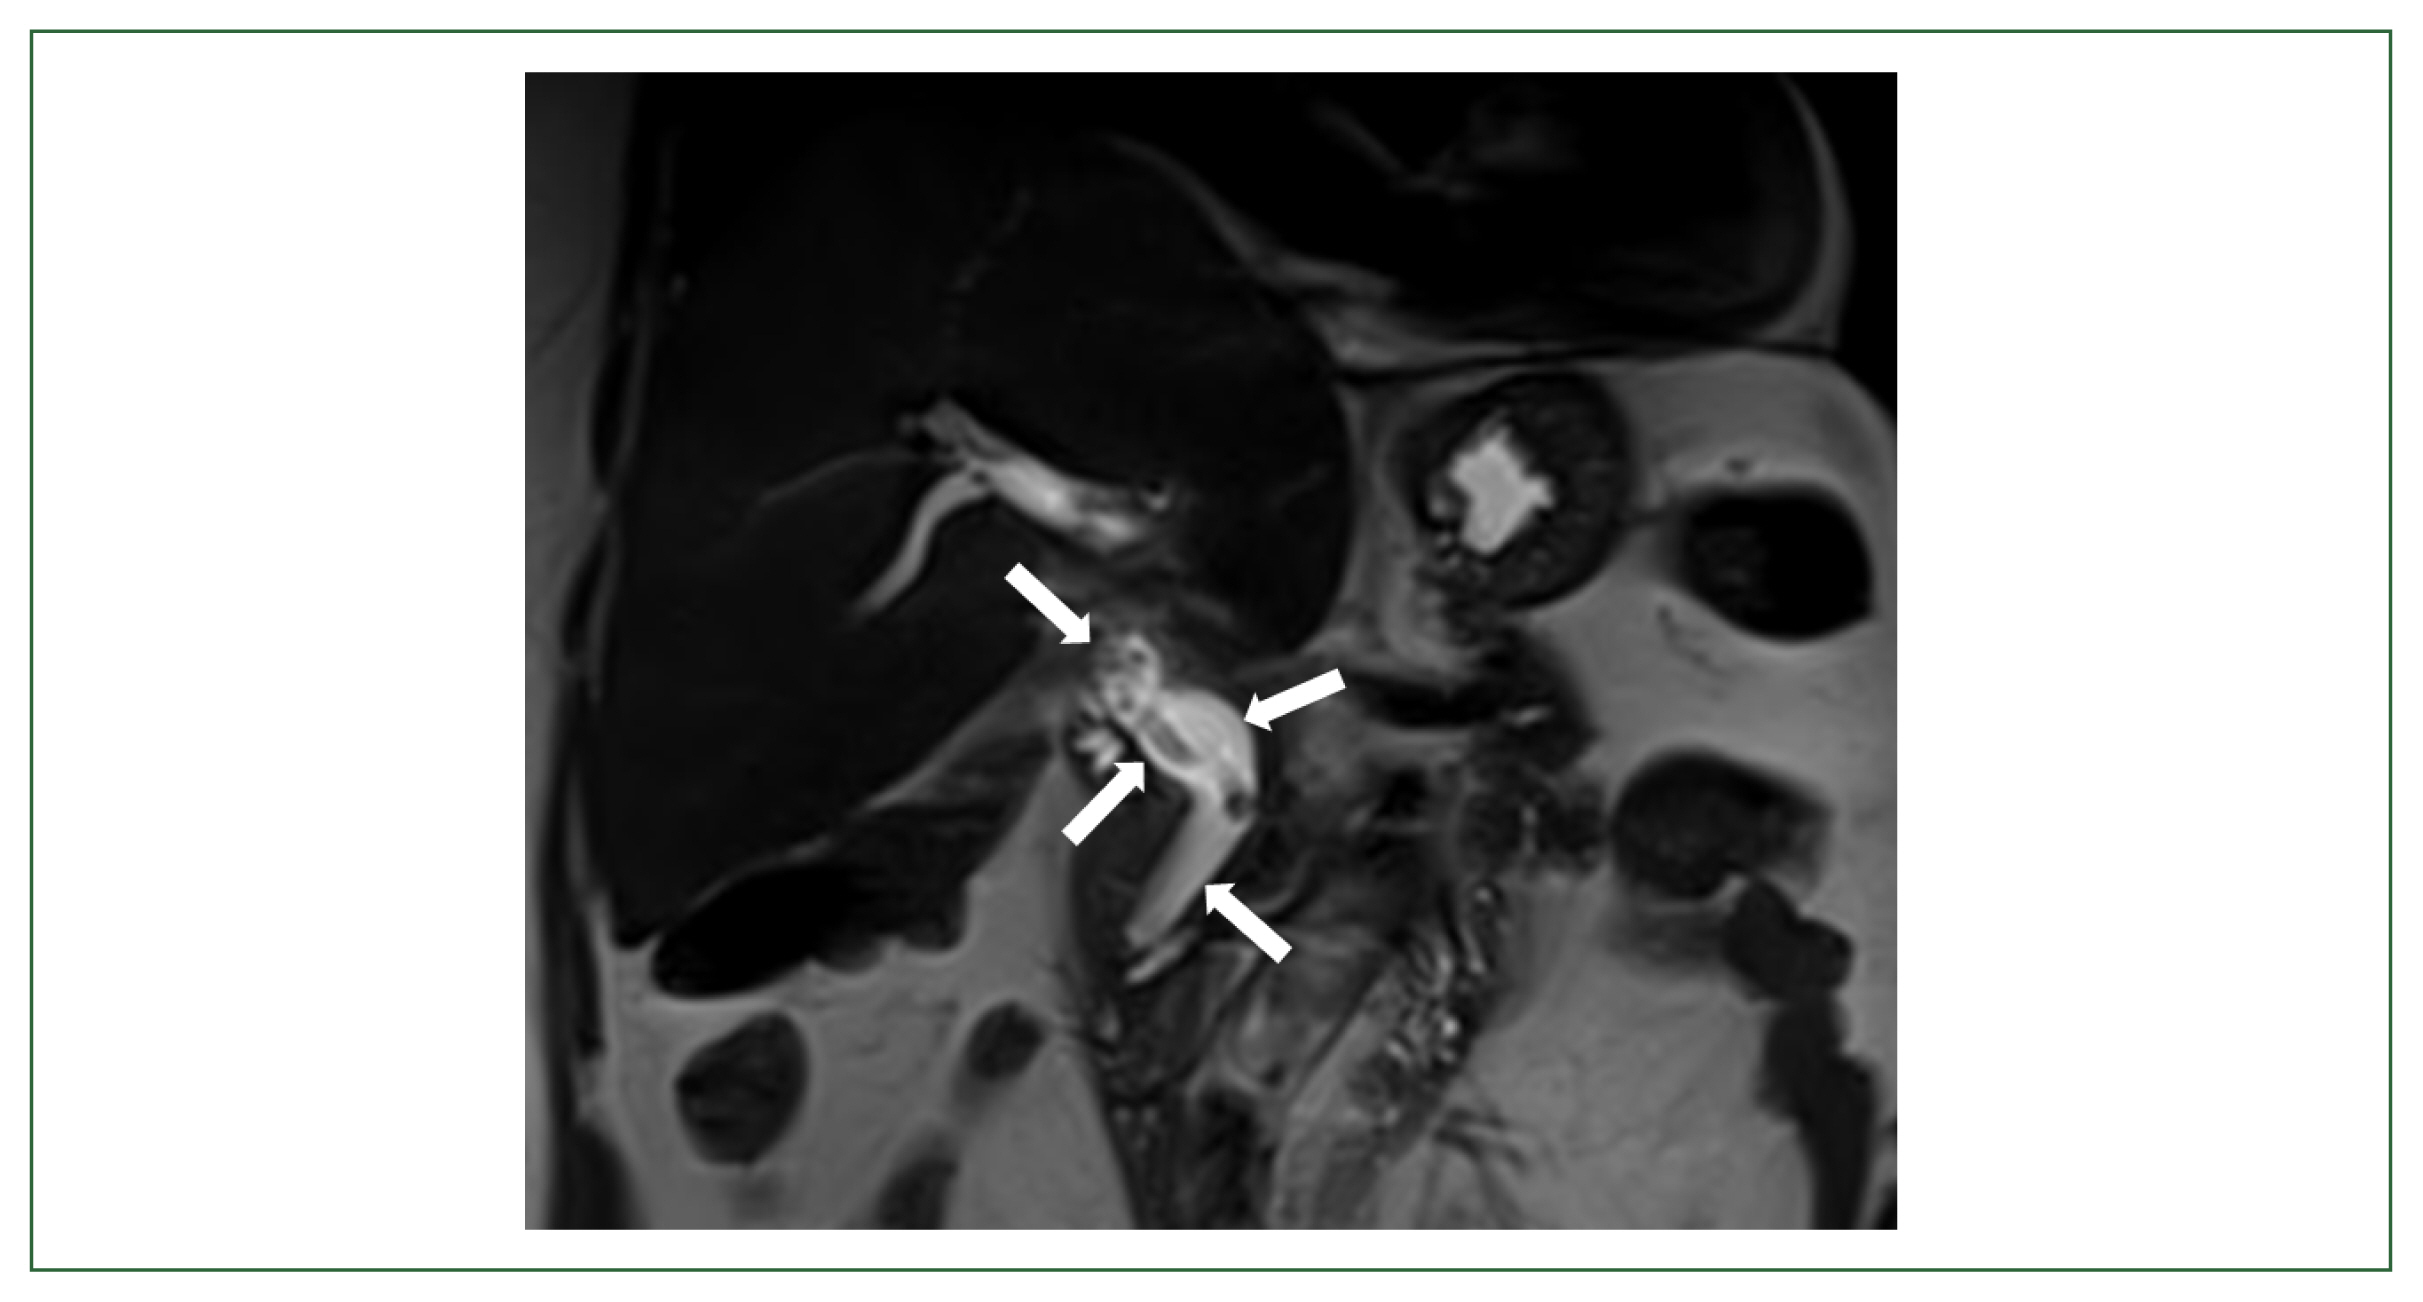

Biliary ascariasis misidentified as a biliary stent in a patient undergoing liver resection

Hochang Chae, Suk Won Suh, Yoo Shin Choi, Hee Ju Sohn, Seung Eun Lee, Jae Hyuk Do, Hyun Jeong Park

Parasites Hosts Dis 2023;61(2):194-197.

Published online May 23, 2023

DOI: https://doi.org/10.3347/PHD.23012

Ascaris lumbricoides causes one of the most common soil-transmitted helminthiases globally. The worms mostly infect the human small intestine and elicit negligible or nonspecific symptoms, but there are reports of extraintestinal ectopic ascariasis. We describe a rare case of biliary ascariasis mistaken for biliary stent in a 72-year-old female patient with a history of liver resection. She visited our outpatient clinic complaining of right upper quadrant pain and fever for the past week. She had previously undergone left lateral sectionectomy for recurrent biliary and intrahepatic duct stones 2 years ago. Besides mildly elevated gamma-glutamyl transferase levels, her liver function tests were normal. Magnetic resonance cholangiopancreatography revealed a linear filling defect closely resembling an internal stent from the common bile duct to the right intrahepatic bile duct. A live female A. lumbricoides adult worm was removed by endoscopic retrograde cholangiopancreatography (ERCP). Despite a significant decrease of the ascariasis prevalence in Korea, cases of biliary ascariasis are still occasionally reported. In this study, a additional case of biliary ascariasis, which was radiologically misdiagnosed as the biliary stent, was described in a hepatic resection patient by the worm recovery with ERCP in Korea.